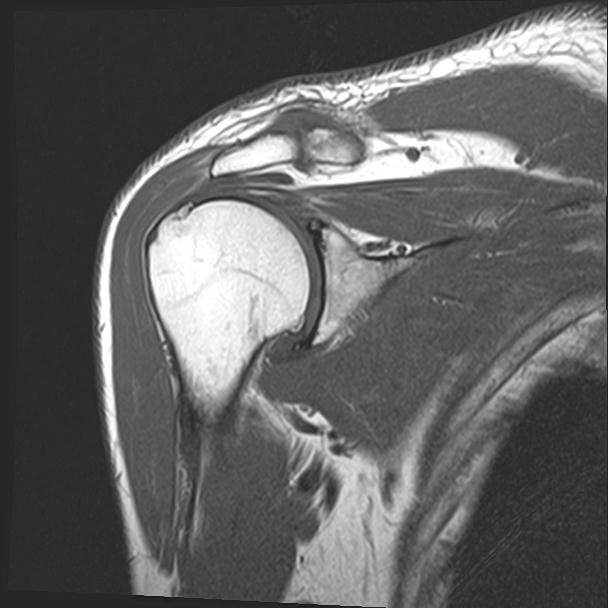

60058 3/9 11/4 右肩 2R+MRI 73歳男性 肩腱板損傷